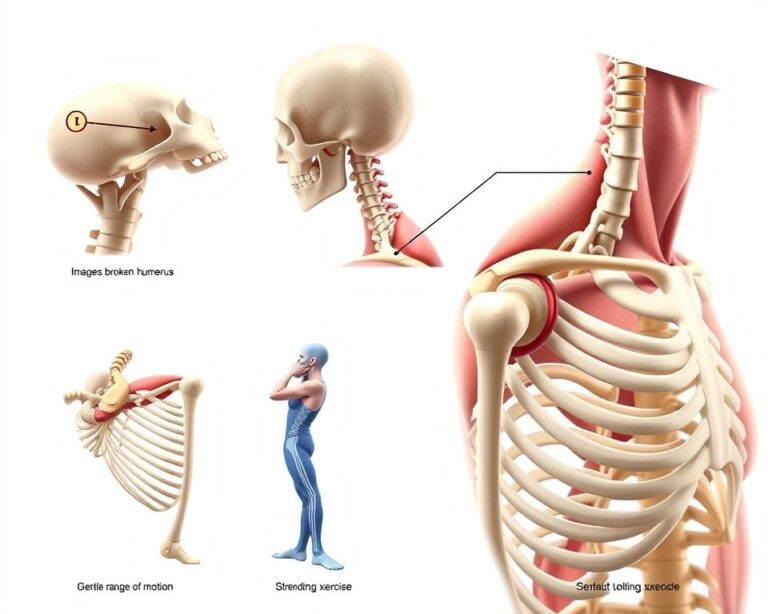

Zastosowanie terapii manualnej i instrumentalnej

W pierwszej fazie skupiamy się na kontroli obrzęku. Krioterapia i ultradźwięki z lekami przeciwzapalnymi przyspieszają gojenie. Prądy TENS skutecznie blokują sygnały bólowe, umożliwiając rozpoczęcie ćwiczeń.

Gdy ostry stan minie, terapeuta wprowadza techniki mobilizacji. Delikatne rozciąganie przywraca elastyczność, a ćwiczenia izometryczne wzmacniają mięśnie bez obciążania stawu. W przypadku zerwania torebki często stosuje się specjalne taśmy stabilizujące.

Jak bezpiecznie odzyskać sprawność?

Ćwiczenia zaczynaj od ruchów biernych – np. delikatnego zginania palców z pomocą drugiej ręki. Stopniowo wprowadzaj opór: gumy oporowe lub małe hantle wzmacniają mięśnie bez przeciążania torebki stawowej. Kluczowa jest regularność – nawet 10-minutowe sesje 3 razy dziennie przynoszą efekty.

W przypadku kostki sprawdza się trening propriocepcji. Stań na jednej nodze na niestabilnym podłożu (np. poduszce). To poprawia czucie głębokie i stabilizuje staw.